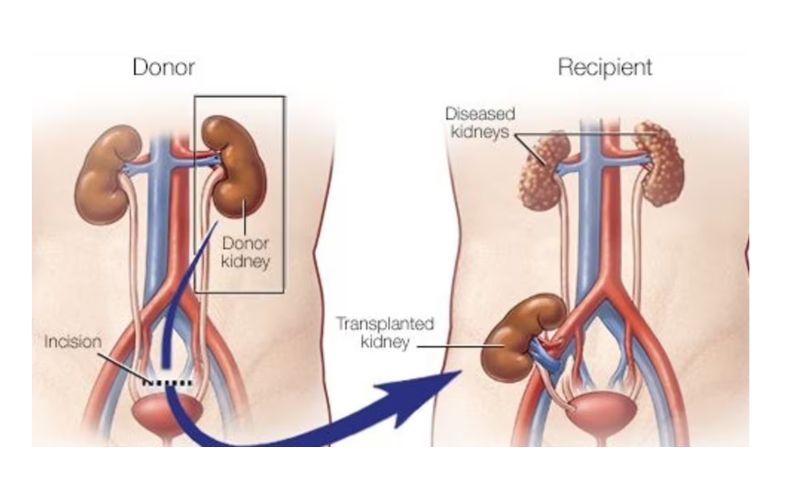

Kidney transplantation

Kidney transplantation is a life-saving procedure for patients with end-stage kidney disease or kidney failure. It involves replacing a non-functioning kidney